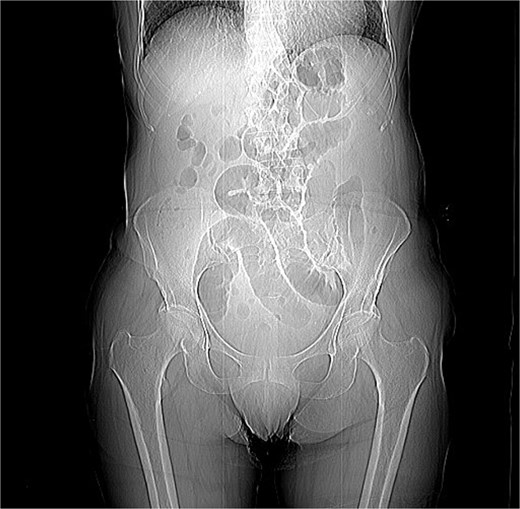

A 76-year-old female patient presented to the emergency department with abdominal pain and vomiting. A standard radiography (Fig. 1) and a contrast-enhanced abdominal CT scan revealed an intestinal obstruction caused by intussusception of the terminal ileum into the cecum (Figs 2 and 3). Laboratory tests showed elevated C-reactive protein levels and leukocytosis. Her medical history was significant for bilateral carotid artery stenosis (under treatment with clopidogrel), mild obstructive sleep apnea syndrome, and hypertension.

The patient exhibited classical symptoms of bowel obstruction (abdominal pain and vomiting), confirmed by imaging studies. The elevation of inflammatory markers suggested a more advanced disease stage, possibly with localized inflammation or ischemia. The patient’s prior medical history did not directly influence the intussusception, but these comorbidities required careful perioperative management. The CT scan clearly demonstrated intussusception of the terminal ileum into the cecum, which is consistent with an ileocolic intussusception, a relatively common form in adults. Given the clinical and radiological findings, the patient underwent urgent laparoscopic right hemicolectomy with extracorporeal anastomosis.